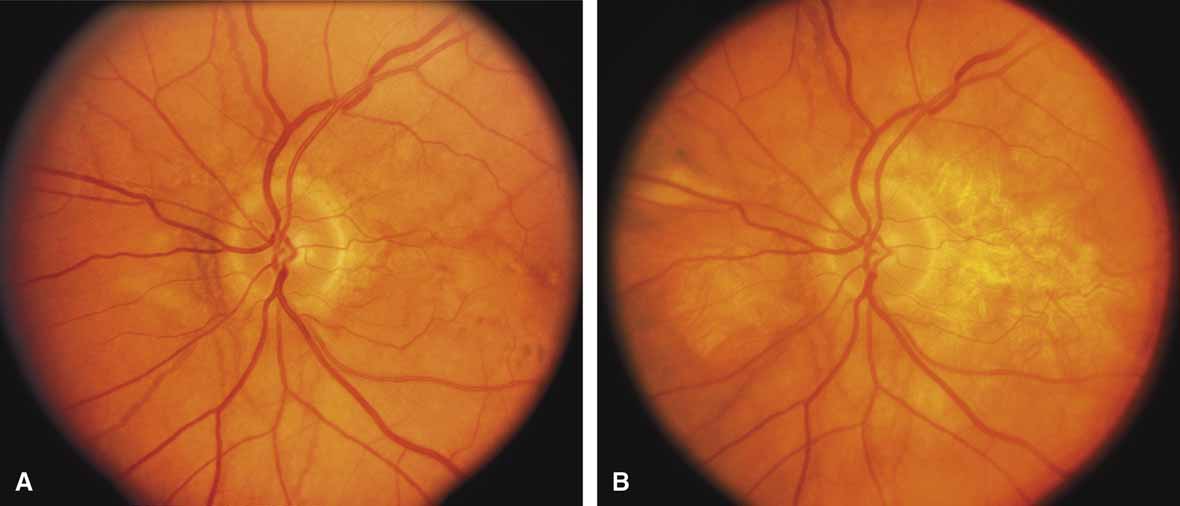

Diffuse choriocapillaris atrophy, also called diffuse choroidal sclerosis and diffuse choroidal angiosclerosis, can be inherited either as an autosomal dominant or, less commonly, as a recessive trait. Certain mutations of the peripherin/RDS gene have also been associated with diffuse choriocapillaris atrophy.18 The disorder is characterized by progressive thinning and loss of choriocapillaris beginning in midlife and resulting in severe loss of vision by later years (Fig. 9). Although the disease in most families is quite consistent among affected individuals, both diffuse and regional central choriocapillaris atrophy have been reported in the same family, suggesting that these two disorders are interrelated.11 Symptoms may include night blindness, loss of central vision, and loss of peripheral vision—the latter feature distinguishing this disorder from the regional form of central choriocapillaris atrophy. Fluorescein angiograms show thinned or absent choriocapillaris with prominent medium and large choroidal vessels throughout the retina. Eventually, mild pigment dispersion and clumping occur in the peripheral retina as the retinal pigment epithelium and overlying retina become affected, but the picture is still dominated by the atrophy of the choroid. The electroretinogram, except in the earliest stages, is usually severely abnormal and eventually becomes unrecordable. The EOG is abnormal early in the disease.